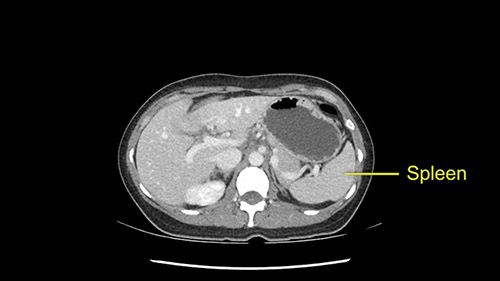

As I review the CT scan, we have both arterial and venous phases, the tumor is obvious. But I’ll start by saying that the liver itself does not appear to be cirrhotic to my eye. It’s got a normal contour and allied to that, that I do not see evidence of portal hypertension. The spleen is normal, there’s no collateral vessels. The tumor itself, I measured maximally at about 11 centimetres in diameter and I’m told the alpha fetoprotein is very high (over 10000), which is entirely consistent with this being a solitary hepatocellular carcinoma that is very exophytic. It seems to emanate off the inferior margin of Segment 3 (because that’s the falciform). I’ll start by saying that this is not transplantable. The tumor exceeds our guidelines for transplantation, but it's likely resectable based on normal liver and no portal hypertension.